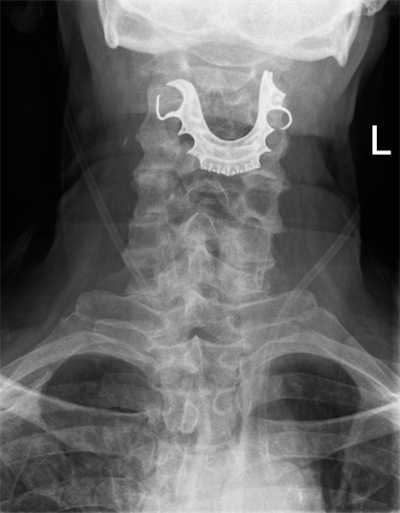

An ENT exam revealed a "metallic semicircular object overlying the vocal cords and completely obstructing their view." When the doctor told this to the patient, he revealed that he had lost his partial dentures during his surgery stay eight days earlier.

Anteroposterior neck radiograph of the 72-year-old man. Image courtesy of BMJ Case Reports 2019.The patient received emergency surgery to remove the dentures from his throat. He was discharged six days later but returned after another case of bleeding. The discharge and readmission cycle occurred several more times until doctors realized he had a torn artery where the dentures had been.